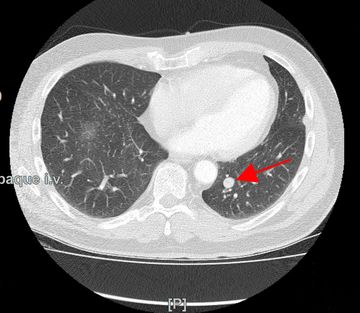

Lungenkrebs

Lungenkrebs befällt etwa 25 Prozent aller Krebskranken und gilt als häufigster Tumor beim Mann. Doch auch immer mehr Frauen sind betroffen. Die chirurgische Therapie ist für uns Mittel der Wahl, sofern keine Fernmetastasen vorhanden sind. Dabei können wir in unserer Klinik technisch hoch anspruchsvolle Lungenoperationen auf endoskopische Weise videoassistiert vorgenommen werden.

Lungenmetastasen

Werden neben Lungenkrebs auch Lungenmetastasen diagnostiziert, stellt das die Medizin vor höchste Herausforderungen. Nur wenige Kliniken sind darauf spezialisiert, bei dieser Erkrankung chirurgisch einzugreifen. Durch besondere fachliche Expertise, einen großen Erfahrungsschatz und die technische Ausstattung ist unsere Klinik Ihr Ansprechpartner, wenn es um die chirurgische Therapie von Lungenmetastasen geht.

Laser-Chirurgie bei Lungenmetastasen

In unserer Klinik für Thoraxchirurgie werden zahlreiche Operationen an der Lunge mit dem modernen 1318NM-Diodenlaser durchgeführt. Das neue Gerät wurde speziell für die Lungenchirurgie entwickelt und hat besondere Eigenschaften, die das Schneiden von Lungengewebe ermöglichen: Mit dem Laser ist der Thoraxchirurg in der Lage, bluttrocken und übersichtlich durch das Lungengewebe zu schneiden. Dadurch können Metastasen und Tumoren, die tief im Lungengewebe liegen, onkologisch sicher entfernt werden. Anhand dieses modernen Verfahrens kann der Thoraxchirurg besonders gewebeschonend vorgehen und zahlreiche Lungenmetastasen entfernen, was mit konventionellen Methoden nicht möglich wäre. So kann die Prognose für den Patienten verbessert werden. Die sogenannte Laser-Metastasektomie ist eine etablierte chirurgische Behandlung, die bundesweit nur in großen Thoraxkliniken vorgenommen wird. Unsere Klinik ist die einzige in Ostwestfalen-Lippe, die Laser-Chirurgie bei Operationen der Lunge anbietet.

- Lungenrundherd (Lungenverschattung)

Gutartige Lungentumoren

Gutartige Lungentumoren sind Bronchialadenome (gutartiger Drüsentumor), Chondrome (Knorpelgeschwulst), darunter am häufigsten die sogenannten Hamartome, Osteome (Knochengeschwulst), Fibrome (Bindegewebsgeschwulst), Lipome (Fettgewebsgeschwulst), Tuberkulome (oft verkalktes Narbengewebe nach abgeheilter Lungentuberkulose). Bis auf Tuberkulome kommen die genannten gutartigen Lungentumoren selten vor. Bei sämtlichen Fragestellungen zu gutartigen Lungentumoren sind wir Ihr vertrauensvoller und kompetenter Ansprechpartner.

Tumornachsorge

Bei der Tumornachsorge geht es darum, nach Therapie eines Krebsleidens eine regelmäßige ärztliche Kontrolle konsequent und dauerhaft durchzuführen. Damit soll bei Patienten mit Lungenkrebs ein erneutes Auftreten des Tumors in der Lunge oder in anderen Organen (Fernmetastasen) frühzeitig zu erkennen. Durch ein frühzeitiges Feststellen eines erneuten Auftretens eines Tumors wird eine frühzeitige Behandlung möglich noch bevor Beschwerden auftreten. In der Nachsorge werden nicht nur körperlichen Symptome, radiologische und Laborkontrollen erfasst, sondern auch psychosoziale Probleme sowie Fragen zur Berufs- und Arbeitsfähigkeit mit dem Patienten diskutiert und Lösungsvorschläge angeboten. Dies geschieht in engem Bezug zum Hausarzt und Lungenfacharzt.

Die Nachsorge soll in enger Kooperation mit dem Hausarzt oder Lungenfacharzt durchgeführt werden. Prinzipiell sind alle Patienten mit einem Lungenkrebs für fünf Jahre der Nachsorge zuzuführen. Dabei schließt sich diese an die Behandlung durch Operation, Strahlen- oder Chemotherapie nahtlos an und sollte bereits nach der ersten Behandlung in der Klinik organisiert werden.